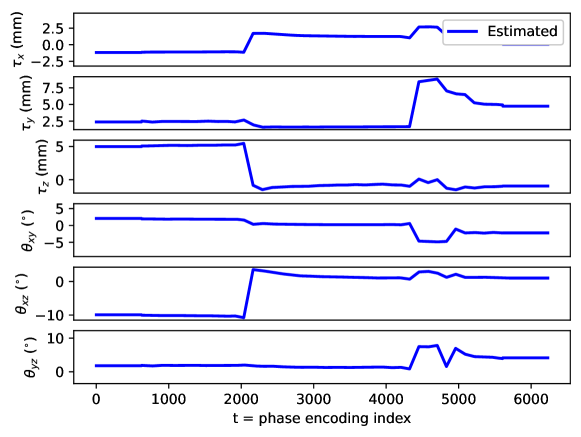

Appendix C Motion parameter estimation

The proposed motion correction algorithm described in Section 2 estimates the rigid motion that the object of interest undergoes during the scan, in order to undo its effect on the reconstructed 3D image. In 3D, the rigid motion is performed by: a plane rotation in the corresponding plane , a plane rotation in the plane, a plane rotation in the plane, a translation in the direction, a translation in the direction, and a translation in the direction (in this order). We adopt the following convention: the direction corresponds to the left-right direction, to the posterior-anterior direction, and to the inferior-superior direction, the plane corresponds to the axial plane, to the coronal plane, and to the sagittal plane. Left/right, anterior/posterior, and inferior/superior are meant from the patient perspective. The orientation of the rotation planes is determined by the right-hand rule.

By design, the prospectively-induced motion for all the experiments detailed in Section 3 follows a step-wise behavior (each step corresponding to a change of pose). In this appendix, we gather the estimated rigid motion parameters for the results shown in Section 4, as a function of time. As noted in the main body of the paper, time is equated to the phase-encoding plane coordinate index, ordered by the corresponding acquisition ordering. We display the estimated motion parameters in Figure 19 (see Sections 3.1, 4.1, Figure 2), Figure 20 (see Sections 3.1, 4.1, Figure 4), Figure 21 (see Sections 3.1, 4.1, Figure 6), Figure 22 (see Sections 3.2, 4.2, Figure 10), Figure 23 (see Sections 3.3, 4.3, Figure 12), and Figure 24 (see Sections 3.3, 4.3, Figure 14).